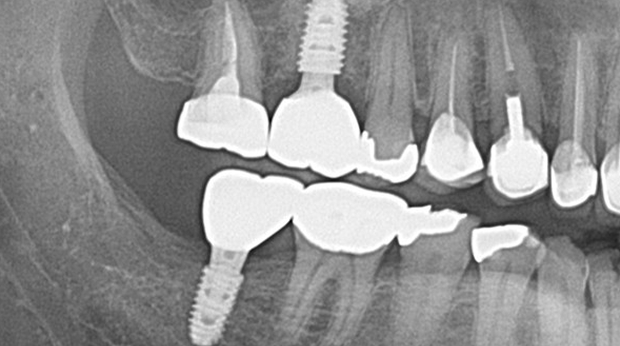

고난도 수술 진료

임플란트와 사랑니 발치는 외과적 시술로 잇몸을 절개하는 외과적 시술은

짧으면 짧을 수록 시술 후 붓기와 통증이 최소화됩니다.

치과의사 경력 14년차 구강외과 전문의가 빠르고 안전하게, 아프지 않게 수술해 드립니다.

치과경력 14년차 구강외과 전문의

연세대학교 치과대학 구강외과 임상 조교수